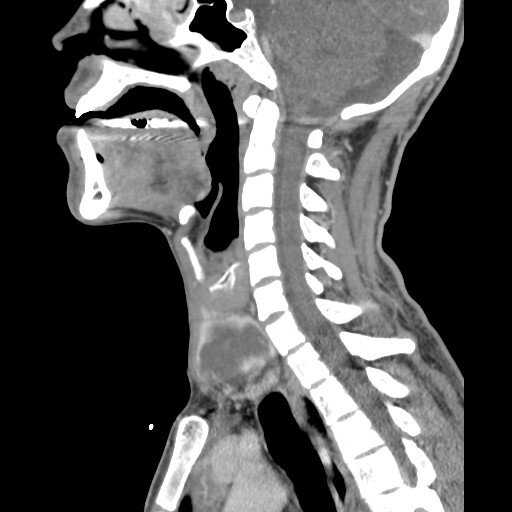

КТ  шеного отдела позвоночникаКТ грудного отдела позвоночникаКТ поясничного отдела позвоночника

• Шейный отдел позвоночника - достаточно часто страдает от костных разростаний: остеофитов, остеоартроза, шейного спондилеза. Траматическим повреждения подвержена зона крепления черепа с первым шейным позвонком - краниовертебральный переход. Краниоцервикальный переход состоит из кости, которая образует основание черепа (затылочная кость), и первых двух позвонков (шейных позвонков), атланта и осевого позвонка. С помощью мультиспиральной компьютерной томографии позвоночника у врачей есть возможность диагностировать заболевания большого затылочного отверстия, платибазию кости, базилярную инвагинацию, ассимиляцию атланта, синдром Клиппеля-Фейля, сращение двух первых позвонков.